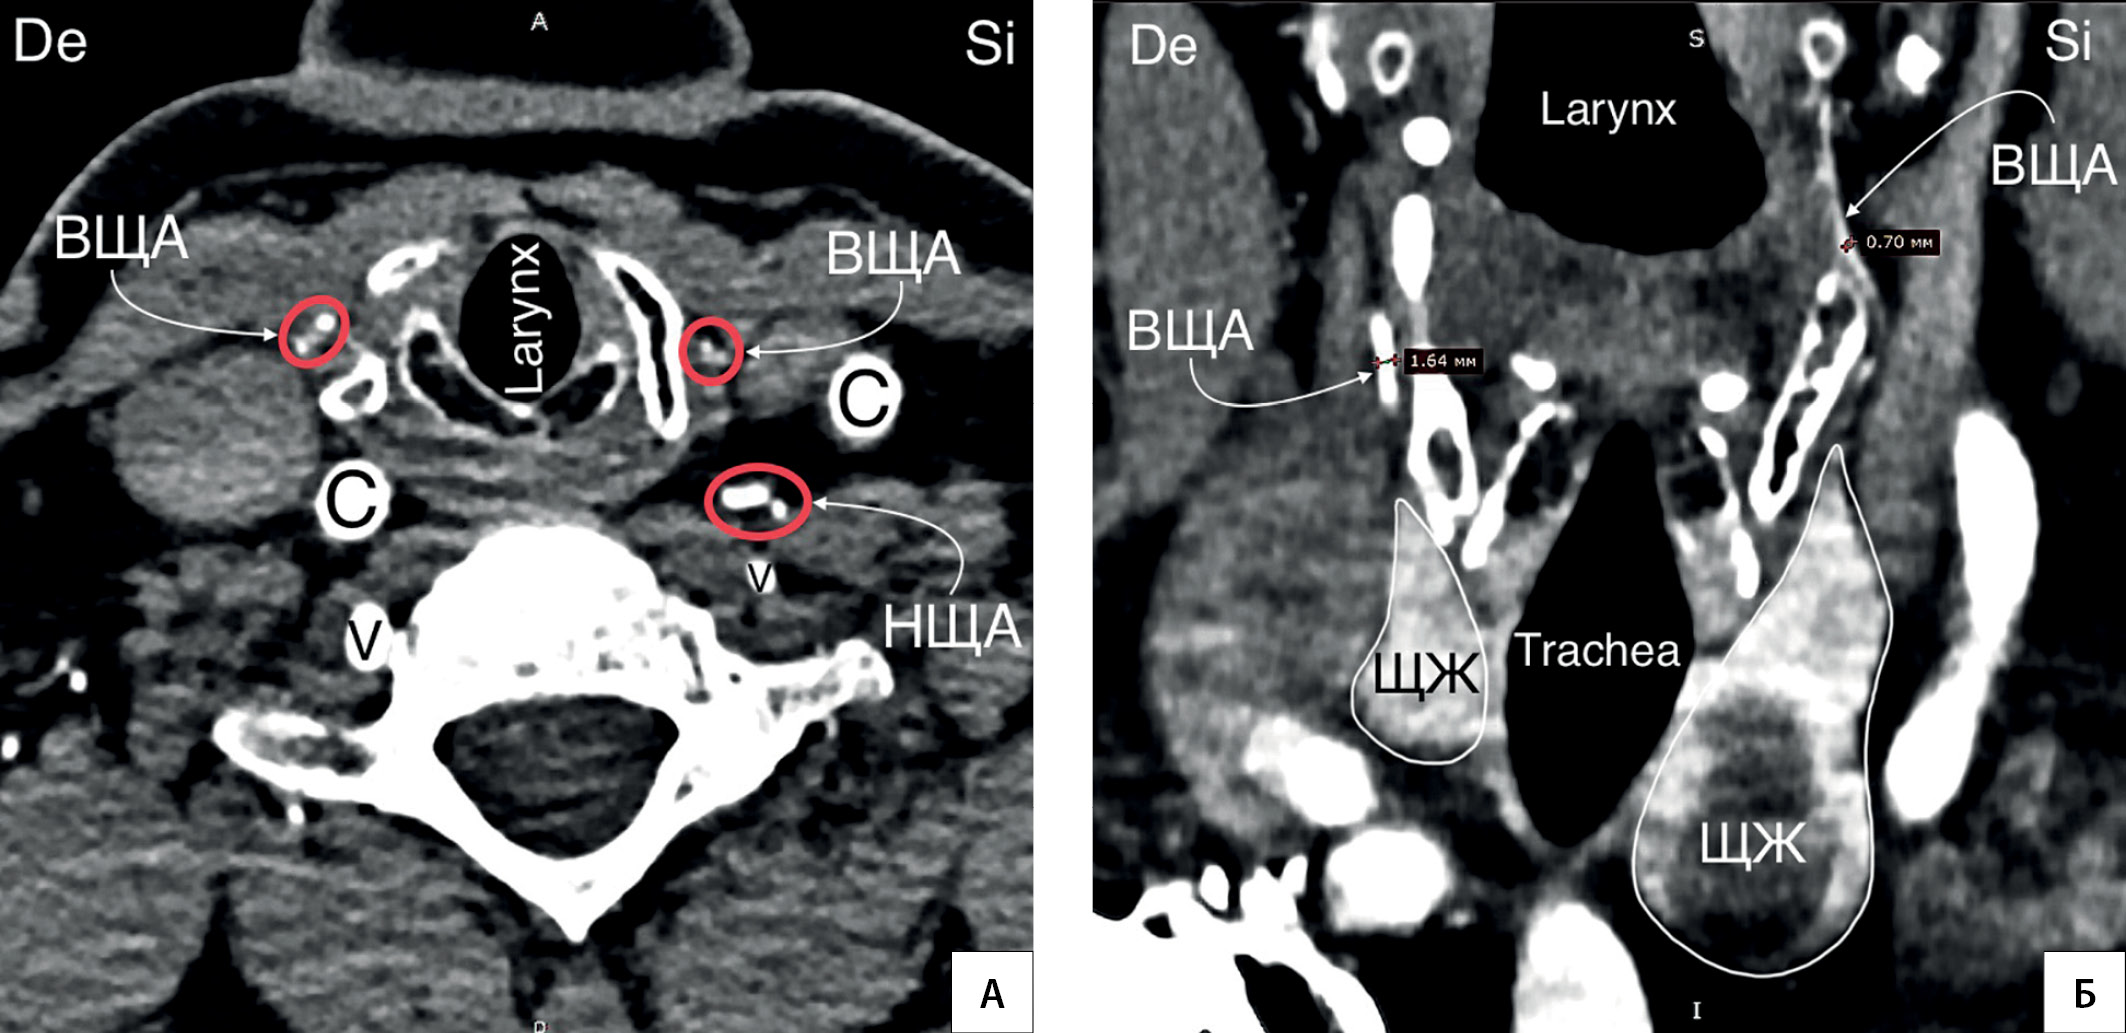

14. Рисунок 14. Агенезия правой НЩА. А — КТ-ангиография (горизонтальный срез). Правая НЩА не контрастируется. Правая ВЩА крупнее левой ВЩА. Б — КТ-ангиография (фронтальный срез). Правая ВЩА (1,6 мм) крупнее левой (0,7 мм). C — a. carotis communis; V — a. vertebralis; De — dextra; Si — sinistra. | |